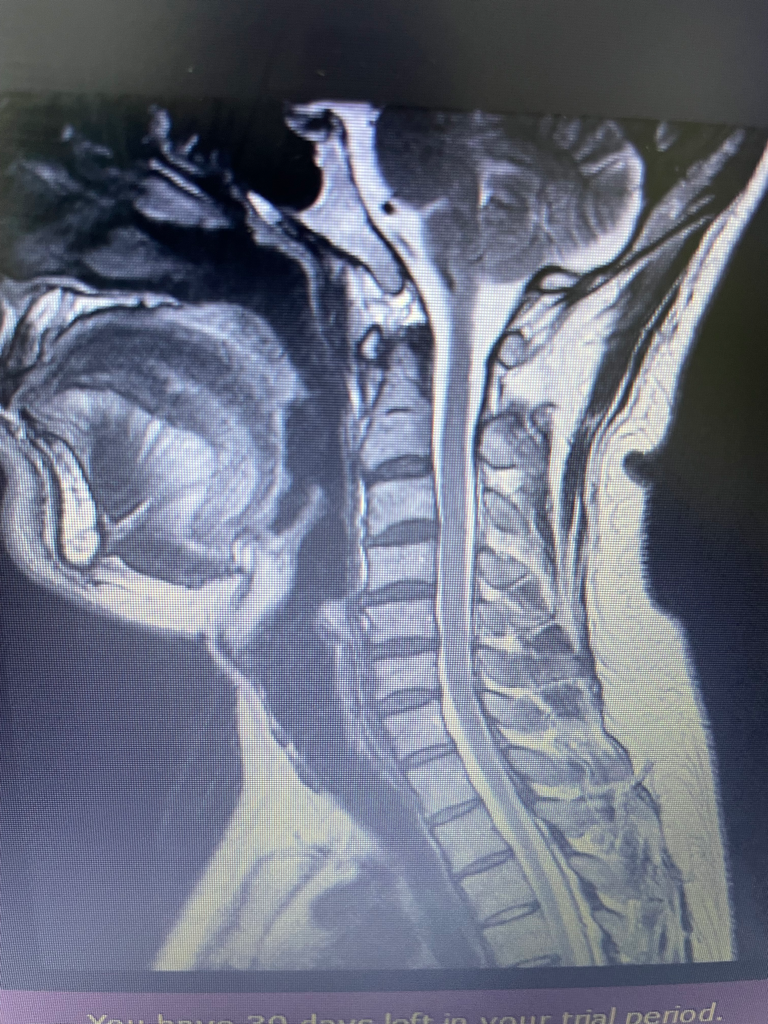

병원에서 목디스크 시술 받았는데요 목디스크 초기인가요 이니면 팽윤 정도인가요 돌출 이나 탈출 정도일까요 ? 어떤 병원은 목디스크 보다는 근육문제라 하던데

정확하게 판단하기는 어렵지만 사진만 보았을때는 팽윤 정도로 보입니다. 시술은 영상뿐만 아니라 증상을 종합하여 시행하게 됩니다.

관련 전공이 아니라 조심스럽지만 , 개인적으론

저명한 신경압박은 보이지 않는듯 합니다만

그 외 소견은 잘 모르겠네요.